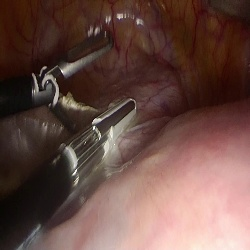

Large Vision-Language Models offer a new paradigm for AI-driven image understanding, enabling models to perform tasks without task-specific training. This flexibility holds particular promise across medicine, where expert-annotated data is scarce. Yet, VLMs' practical utility in intervention-focused domains--especially surgery, where decision-making is subjective and clinical scenarios are variable--remains uncertain. Here, we present a comprehensive analysis of 11 state-of-the-art VLMs across 17 key visual understanding tasks in surgical AI--from anatomy recognition to skill assessment--using 13 datasets spanning laparoscopic, robotic, and open procedures. In our experiments, VLMs demonstrate promising generalizability, at times outperforming supervised models when deployed outside their training setting. In-context learning, incorporating examples during testing, boosted performance up to three-fold, suggesting adaptability as a key strength. Still, tasks requiring spatial or temporal reasoning remained difficult. Beyond surgery, our findings offer insights into VLMs' potential for tackling complex and dynamic scenarios in clinical and broader real-world applications.